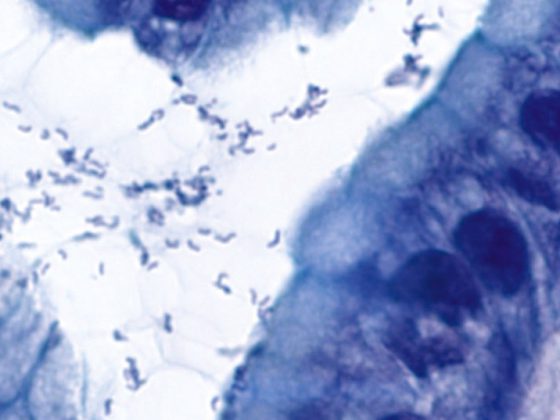

helicobacter2

• Helicobacter pylori Infektion

Eradikationsrate ist gegen Risiko einer Resistenzbildung abzuwägen